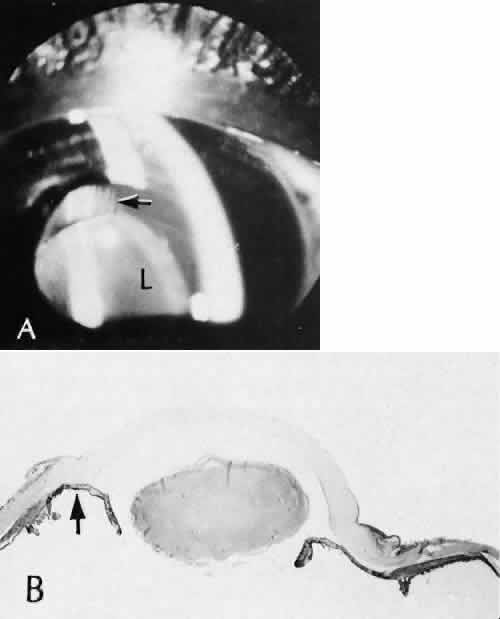

CATARACT EXTRACTION The cataract incision is made into the anterior chamber in such a way as not to injure the trabecular meshwork or unduly injure the cornea. The traditional cataract wound extends from the episcleral tissue posterior to the surgical limbus (defined by the insertion of the conjunctiva and Tenon's capsule) through the corneoscleral tissue to enter the anterior chamber by perforating Descemet's membrane anterior to Schwalbe's line. Clear corneal cataract incision involves only the peripheral cornea. Special circumstances may occur in which a more posterior or anterior route of incision may be desirable.55,56 The most reliable histologic landmark of a healed cataract incision (Fig. 14) is a hiatus of peripheral Descemet's membrane. The cut edges of Desce-met's membrane will curl inward toward the sclera.Endothelial cells may be absent or may have produced a new, thin, periodic acid-Schiff-positive Descemet's membrane over exposed corneal stroma. Occasionally, a fibrous plaque is present at the level of Descemet's membrane. This plaque is another example of fibrous metaplasia, in this instance of the corneal endothelial cells. The corneal stromal portion of the wound may be difficult to identify histologically, except in the early stages of healing. Clues to the position of the intrastromal tract include residual suture material, malorientation of collagen bundles, vascularization along the route of the incision, or incarceration of pigment, lens capsular remnants, or fragments of Descemet's membrane. The superficial portion of the wound tends to heal most completely. Breaks in Bowman's membrane will be present at the site of suture tracts and clear corneal cataract incisions. Also, areas of epithelial cell inclusion may be present in the substantia propria of the conjunctiva at the conjunctival incision. The capsulotomy incision is anterior to the insertion of the zonules through a relatively thick area of the anterior capsule. Most of the lens epithelial cells are removed with the anterior capsule, although some cells may remain in the region of the equator of the lens (Fig. 15). The residual lens capsule is thinnest at its posterior pole. The anterior capsular flap often adheres to the posterior capsule, encasing any residual cortical material and lens epithelial cells. Lens epithelial cells may grow to form large cells, called bladder cells, or may undergo fibrous metaplasia to form a collagenous plaque. Lens cortex outside the lens capsule has an amorphous appearance and is present only in the earliest postoperative specimens. Peripheral iridectomies are peripheral to the iris sphincter in the midportion of the iris rather than at the less accessible iris base. Complete or sector iridectomies include the iris sphincter but do not extend to the iris base. The edges of an iridectomy may show some rounding of contours, but granulation tissue does not form and iris pigment epithelial proliferation does not generally occur. The iris pigment epithelium may be absent for a considerable distance from an iridectomy produced by laser energy. Intraocular lens material (polymethylmethacrylate) often dissolves during tissue processing. Intraocular lenses containing metal components must be removed before embedding because metal will cause extensive artifacts and damage to microtome knives. Often the only clues to the presence of an intraocular lens are subtle compression changes of the iris or ciliary sulcus. Occasionally, residual synthetic material can be identified by polarized light. Anterior chamber lenses may cause a fibrous reaction in the anterior chamber angle (Fig. 16). Occasionally, collagenous tissue will completely encircle a lens (Fig. 17). Iris-supported lenses are associated with the loss of central iris pigment epithelium or residual nylon suture in the posterior chamber. Posterior chamber lenses are the most difficult to identify unless surrounded by lens remnants, in which case a negative image of the optic or loops can be seen. Sulcus-fixed lenses will show focal areas of iris pigment epithelial depigmentation or iris stromal erosion. The lens loop may displace the peripheral iris to come in contact with the trabecular meshwork. PENETRATING KERATOPLASTY Penetrating keratoplasty is a confusing term. The reference point of the incision is the globe; therefore, when a full-thickness graft is performed, the incision penetrates the globe but perforates the cornea. The concave-convex specimen usually is 7.0 to 8.5 mm in diameter and translucent because of fixation. Gross orientation of the specimen is important if pertinent changes are to be represented in the histologic section. Occasionally, as in keratoconus, the graft is placed axially and causes the pathologic area of thinning to be in an eccentric position in the graft. The area of the cone can be detected by observing the shadow of the specimen cast by a strong light. Descemet's membrane will not curl as extensively toward the stroma, as seen with in vivo wounds. Occasionally, Descemet's membrane is lost during tissue preparation because the membrane is easily sheared free of the corneal stroma. With repeat penetrating keratoplasty operations, the original corneal incision may or may not be represented in the specimen because of variations of size and position of the second graft procedure. Penetrating keratoplasty wounds in enucleation specimens can be identified by the changes in Descemet's membrane (Fig. 18). Because the donor tissue is often from a younger person, Descemet's membrane of the graft is thinner than the peripheral membrane of the host. Occasionally, redundant Descemet's membrane from the host intentionally will be left behind in this region by the surgeon. Often small areas of retrocorneal fibrous plaque mark the posterior area of the wound, even in cases of clinically uncomplicated wound healing. In time, the stromal portion of the wound may be undetectable histologically although some malorientation of the collagen lamellae often is present. Bowman's membrane does not reform as a distinct membranelike structure. Needle tracks or suture material may be seen in the tissue adjacent to the wound. Occasionally, epithelial cells may extend for a considerable distance along these suture tracks. REFRACTIVE SURGICAL PROCEDURES Laser in situ keratomileusis (LASIK) has become the predominant surgical procedure for the correction of refractive error, particularly myopia.57 An estimated 1.5 million LASIK procedures were performed in 2000.58 The advantages over previous laser procedures, particularly photorefractive keratectomy, include less postoperative pain, faster return of visual function, less regression of refractive effect, and less central corneal haze.58 The LASIK procedure provides access to the central corneal stroma with a mechanical oscillating steel microtome to create a lamellar flap. The microtome is stabilized to the anterior globe by a suction device that can raise the intraocular pressure to levels between 80 and 360 mm Hg, depending on the type of microtome used.59 The hinge of the flapmay be placed horizontally or vertically. An excimer laser removes a calculated amount of corneal stroma according to an algorithm determined for the type and amount of refractive error. The central corneal epithelium is not disturbed. The anterior corneal flap is repositioned without sutures. Central corneal thickness has become a critical fac-tor in determining the amount of tissue that can be safely removed to protect corneal endothelial cells. In most cases, the safety zone for the posterior cor-neal stroma has been established at 250 microns.60–63This zone is necessary to reduce the risk of endothelial cell damage and the risk of postoperative iatrogenic corneal ectasia.61 Several studies have shown a marked variation of normal central corneal thick-ness in a range of 472 to 651 m.64,65 The central corneal thickness is independent of axial length, age, sex, horizontal corneal diameter, and refractive error.64 Preoperative pachymetry is therefore mandatory. With several microkeratomes, scanning electron microscopy may show a fine undulating contour up to 0.2 mm at the border of the lamellar bed and flap. This feature is formed as chatter lines parallel to the cutting edge of the microkeratome blade (Fig. 19). The frequency of the chatter may relate to the nonlinear pass of the microkeratome. Chatter is absent in rotary keratomes and keratomes using a high oscillation frequency.66–68 The refractive outcome of all refractive procedures depends on the wound healing response of the corneal epithelium and stroma. The wound healing response in LASIK is found primarily at the region of epithelial transection at the edge of the flap. In animal models, epithelial reaction and production of type IV collagen is seen at the most peripheral edge of the lamellar flap. Gelatinase B, which is important in basement membrane remodeling, was localized to the basement membrane zone and superficial stroma.69 There is minimal to no inflammatory infiltrate along the margins of the lamellar bed. However, disorganization of the extracellular matrix extending to a depth of 5 μ from the surgical margin has been observed for as long as 9 months after surgery. The disorganization of the extracellular matrix suggests that the wound healing process is incomplete for a long period after surgery.70 Keratocytes in the region of the edge of the flap can be strongly stimulated by epithelial cell cytokines in part because of the localized absence of Bowman'smembrane. The potential for anterior stromal haze in the setting of LASIK is limited to the flap border, whereas in photorefractive keratectomy, the haze is most likely to occur centrally.71,72 In LASIK, there is a combination of intact corneal epithelium not producing cytokines and an intact Bowman's membrane limiting the diffusion of cytokines to influence underlying keratocytes.73,74 With LASIK, however, there appears to be increased interface reflectivity associated with thin lamellar flaps. There also appears to be a loss of keratocytes in the most anterior flap stroma in the period between 6 months and 2 years after surgery.75 Ophthalmic and maxillary branches of the trigeminal nerve supply the cornea. Most of the corneal stromal nerve supply is within the anterior two thirds of the stroma. Corneal sensation is essential for the maintenance of normal corneal physiology. The LASIK procedure transects nearly all corneal nerves except those located in the hinge of the flap. Corneal sensitivity is reduced 1 to 2 weeks after the LASIK procedure. The highest sensitivity is greatest at the hinge. Sensation has been noted to return during the next 6 months.76 Return of tensile strength to the lamellar incision of the corneal stroma is limited after LASIK. In an animal model, Maurice estimated that the wound healing process reestablished only 50% of the native tensile strength of the stroma.77 This lack of intrastromal adhesion is expressed in a rate of flap dislodgement estimated to be between 1% to 2% of LASIK procedures.78,79 GLAUCOMA SURGICAL PROCEDURES Laser trabeculoplasty causes distortion, shrinkage, and scarring of the collagenous beams of the trabecular meshwork. No perforation occurs into the area of Schlemm's canal. Cyclocryotherapy, cyclodiathermy (Fig. 20), and therapeutic ultrasonography apply energy directly to the pars plicata and cause lysis of the ciliary muscle and occlusion of the vascular supply, leading to extensive necrosis and scarring. Pressure lowering is accomplished by a reduction of aqueous production. Heat applied to the sclera may cause necrosis and localized scleral thinning. Cold applied to the sclera, unless extreme, does not cause any clinical or histologic changes. Cyclodialysis (Fig. 21) creates a cleft between the sclera and the longitudinal muscle of the ciliary body. Aqueous passes directly from the anterior chamber into the suprachoroidal space. Histologically, the longitudinal muscle of the ciliary body is disinserted from the scleral spur. Diaphanous tissue often is present in the suprachoroidal space along the route of filtration. The presence of this tissue differentiates the surgical site from artifactual disinsertion of the ciliary body, which is a common artifact of ocular tissue preparation. Many surgical variations are or have been used to create a fistulous tract between the anterior chamber and the episcleral tissue to allow continuous passage of aqueous from the eye. In most cases, the incision is placed at the surgical limbus or more posteriorly in the sclera. The primary variations center on ways to prevent the fistula from closing. Some older procedures simply used a large (2-mm) trephine hole, which was less likely to close than a smaller opening. Cautery placed at the exposed edges of the sclera causes retraction of the wound edge to maintain the fistula. In trabeculectomy, a half-thickness window of posterior peripheral cornea is excised to create a large internal orifice for a fistulous track under a protective scleral flap. Iridencleisis intentionally includes incarceration of iris into the wound to prevent complete scleral healing. Multiple types of foreign material, from horsehair to gold to silicone, in solid or tubular forms, have been fashioned into setons to maintain the opening to the anterior chamber. Some varieties of the setons route aqueous to the equator of the eye, where it is resorbed by the surrounding tissue. Most recently, various agents have been used to control the rate and extent of fibrous proliferation in a surgical fistula. Currently, the most common agent is mitomycin-C, although 5 fluorouracil has been used in the past.80,81 The exact mechanism of action is not known, but limitation of proliferation and migration of cells involved in the wound healing process appears to play a substantial role.82,83 Trabeculectomy specimens usually consist of a tiny portion of pigmented and translucent tissue. The translucent tissue, representing the posterior peripheral cornea, should be oriented perpendicular to the limbus to show Descemet's membrane and any possible trabecular meshwork. Occasionally, clinically unsuspected epithelial ingrowth or neovascular channels may be found (Fig. 22). The neovascular channels can be differentiated from native vessels by their thin adventitial sheaths. RETINAL REATTACHMENT Evidence of previous retinal reattachment surgery is most commonly shown by synthetic bands and other surgical devices on the surface of an enucleated globe. Occasionally, the episcleral fibrous tissue reaction completely encases these materials in a fibrous cloak. The bands and other materials are easily identified after sectioning the globe. The internal signs of surgery include indentation of the sclera and regions of uveal and retinal pigment epithelial depigmentation caused by cryotherapy. The retina may or may not be attached. The synthetic bands are partially soluble in organic solvents used in tissue dehydration for paraffin embedding. The negative image of the material can be seen, usually in the equatorial region, surrounded by a variable degree of fibrous tissue and focal collections of chronic nongranulomatous inflammatory cells (Fig. 23). Occasionally, a foreign body granulomatous reaction is present near degenerating suture. Often the uveal tract in the area of surgery is completely atrophic, as is the overlying retina. Frequently, the retinal pigment epithelium has become depigmented and areas of fibrous metaplasia may be present. Glial proliferation and chorioretinal adhesion may be seen in areas of cryotherapy or diathermy.84,85 Laser photocoagulation of the retina at therapeutic energy levels results in a chorioretinal adhesion between proliferating Müller cells and retinal pigment epithelial cells or between the glial component and the denuded inner surface of Bruch's membrane. The internal limiting membrane of the retina, the basement membrane of the retinal blood vessels, and Bruch's membrane remain intact. Numerous focal areas of choriocapillaris defects remain in the area of photocoagulation. |